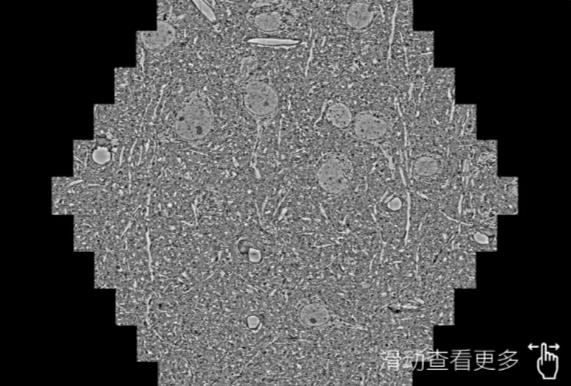

鼠脑切片。左图使用盐城蔡司盐城扫描电镜MultiSEM706对165μmx143pm面积区域成像,耗时仅需1.5秒。右图为鼠脑切片中30μm区域放大效果。样品由芝加哥大学B.Kasthuri提供。

使用蔡司高速盐城扫描电镜MultiSEM对1mm²人脑皮层组织进行高分辨成像,并对其中的各种细胞结构进行三维重构分析。左图展示了2x3mm²组织平面中锥体神经元的三维重构效果。右图显示了局部体积神经元三维重构。图像由哈佛大学chtman实验室提供,渲染图由D. Berger 制作。